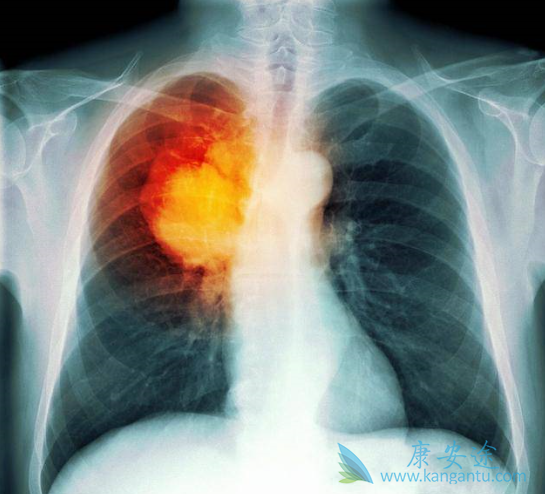

在目前已经公布的不同EGFR-TKI治疗晚期肺癌的III期临床研究中,药物性肝损伤(DILI)的发生率为5%-55.3%,≥3级的发生率为0.4%-26.3%。除阿法替尼外,多数EGFR-TKI主要通过肝脏酶系代谢。有研究认为EGFR-TKI的肝毒性与其活性代谢产物的代谢有关,而诱导的自身免疫性损伤是EGFR-TKI肝毒性的另一种机制。

DILI的临床表现通常无特异性。部分患者可有乏力、食欲减退、厌油、肝区胀痛及上腹不适等消化道症状。淤胆明显者可有全身皮肤黄染、大便颜色变浅和瘙痒等。少数患者可有发热、皮疹、嗜酸性粒细胞增多甚至关节酸痛等过敏表现,还可能伴有其他肝外器官损伤的表现。因此,对于EGFR-TKI治疗过程中出现相应非特异性症状的患者,应考虑到DILI的可能性。但无症状患者,并非一定能排除DILI可能。

血清谷丙转氨酶、谷草转氨酶、碱性磷酸酶、谷氨酰转肽酶和总胆红素等改变是目前判断是否有肝损伤和诊断DILI的主要实验室指标。需要提醒晚期肺癌患者的是,除了应用EGFR-TKI外,若同时服用其他药物包括其他处方和非处方药、传统中药、保健品等前,一定要事先告诉医生,因为肝损伤也可由其他药物引起。